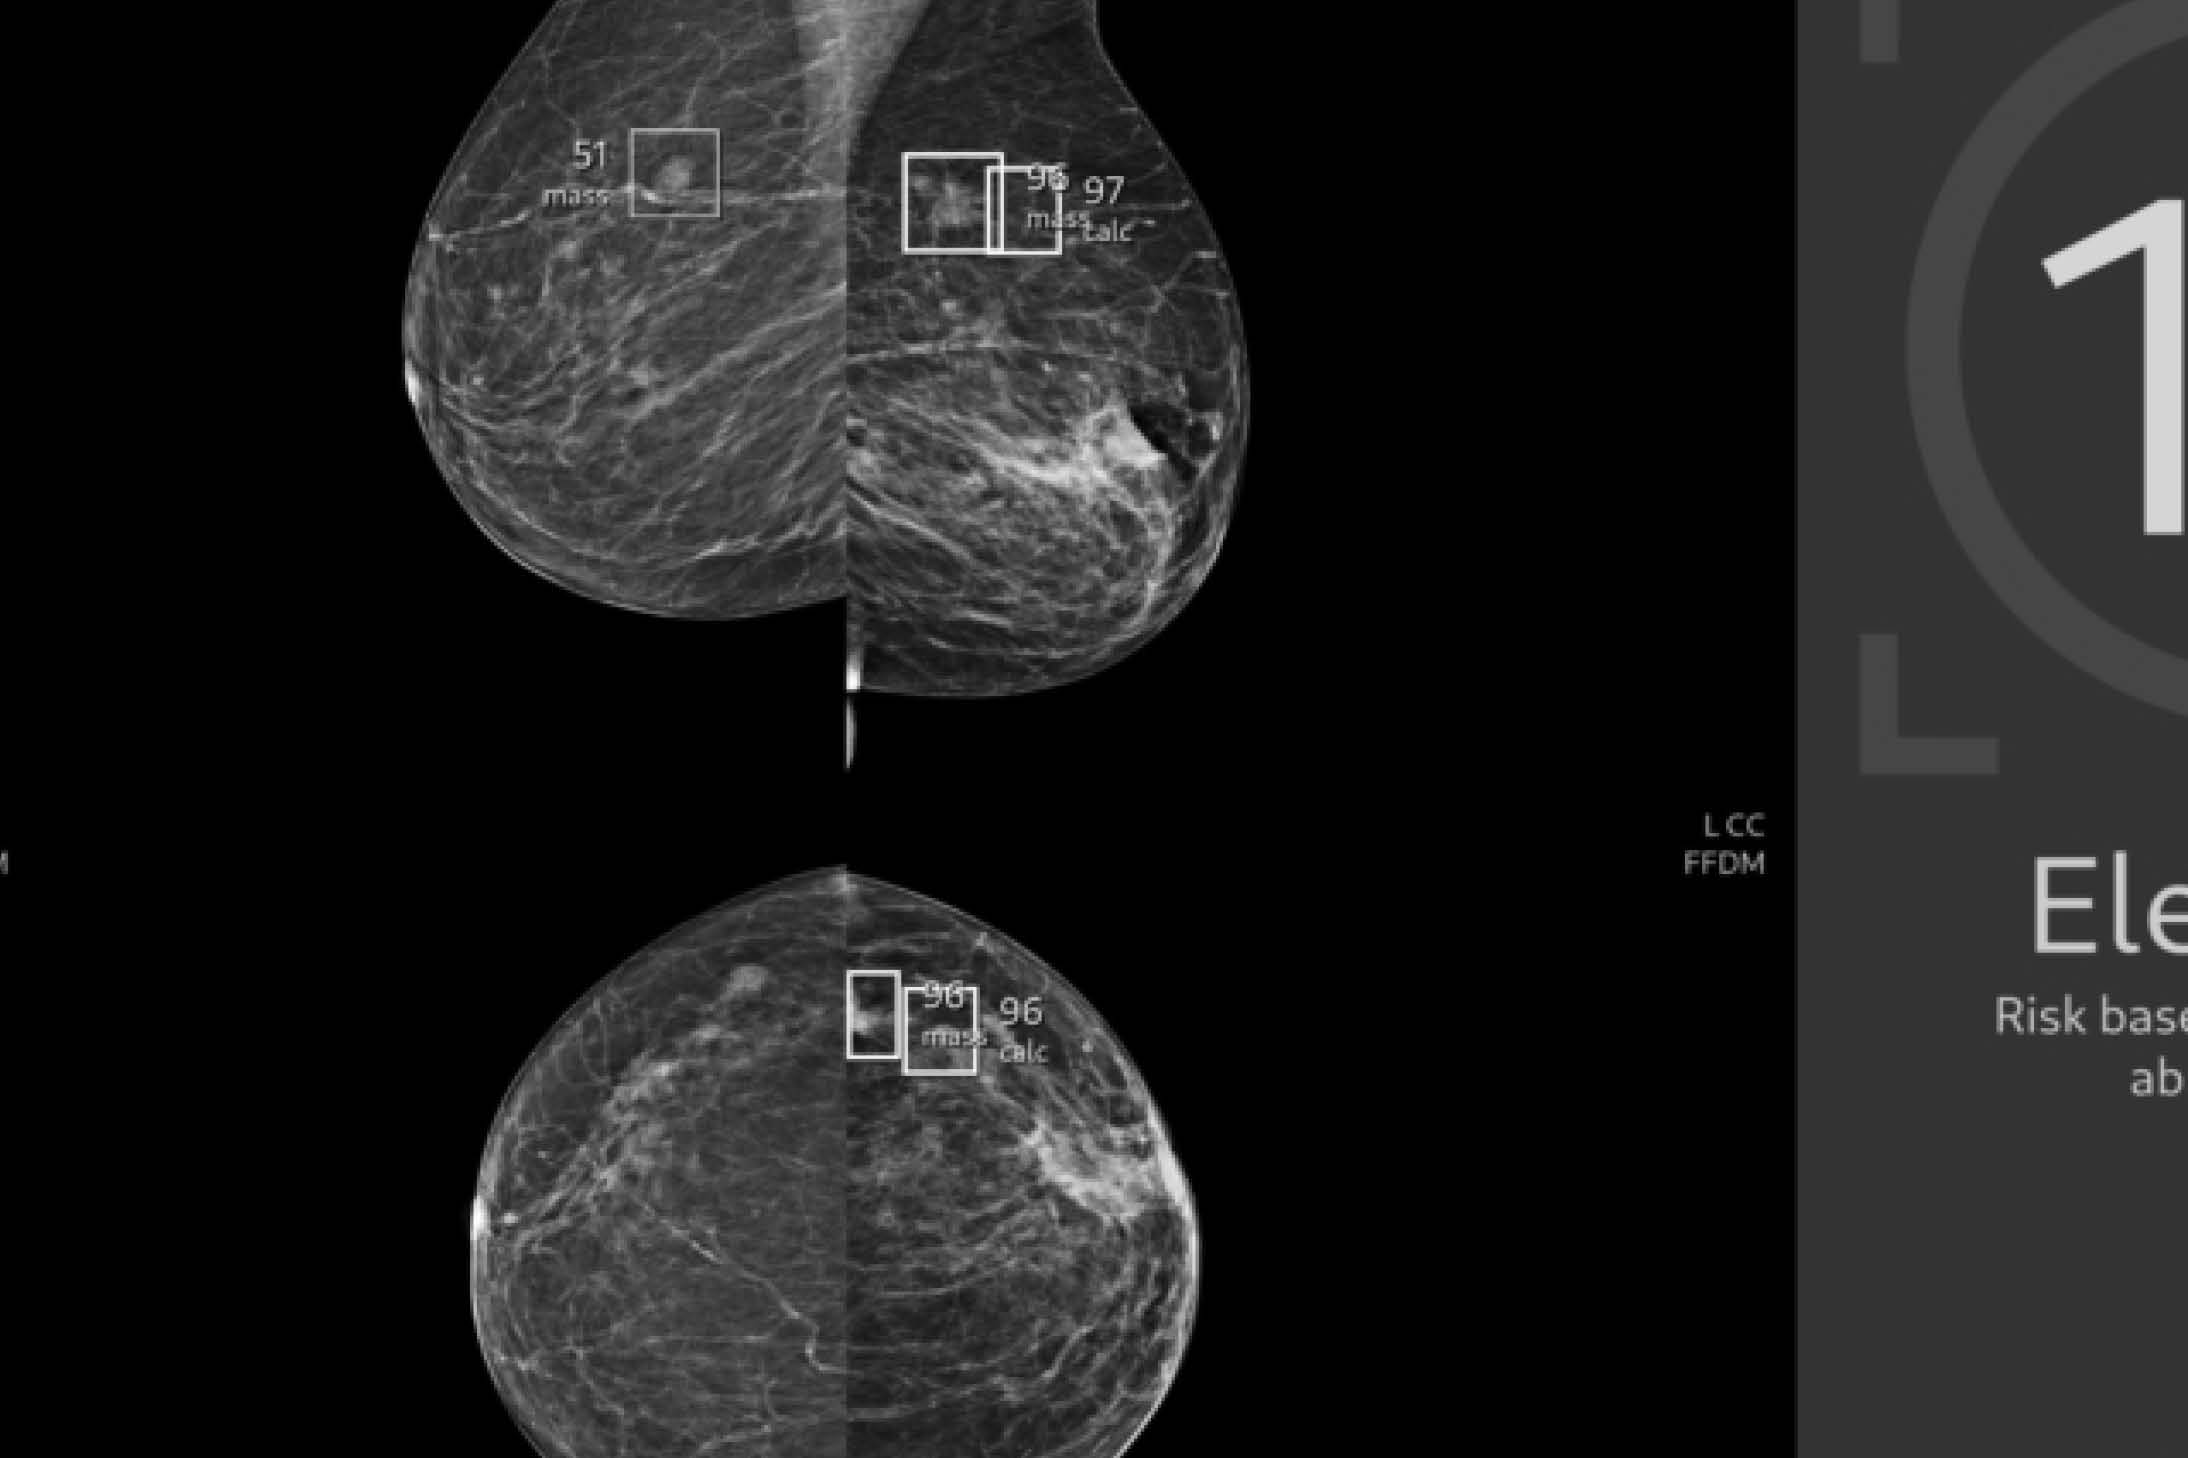

Najde o půlku víc nádorů. Umělá inteligence jako pomoc lékařům v mamografii se má v Česku rozšiřovat

Specialisté v mamografii potřebují hodně dobré oči a klid. Když hledají na monitoru náznaky útvarů, které můžou odkazovat na rakovinu, dívají se do změti bílých čar a ploch, které pro netrénované oko splývají jedna v druhou. I odborníci ale důležité útvary snadno přehlédnou. I proto se snímky takzvaně čtou dvakrát, dvěma nezávislými lékaři. A v pražském screeningovém centru Waltrovka spadajícím pod skupinu EUC rovnou třikrát. Těma třetíma „očima“ je umělá inteligence a projekt ukázal první výsledky.